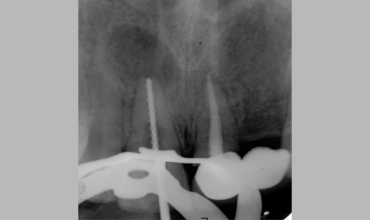

Management Of Internal Root Resorption In Maxillary Central Incisor Pre-operative Radiograph Removal Of Granulation Tissue With Ultra

Management Of Internal Root Resorption In Maxillary Central Incisor